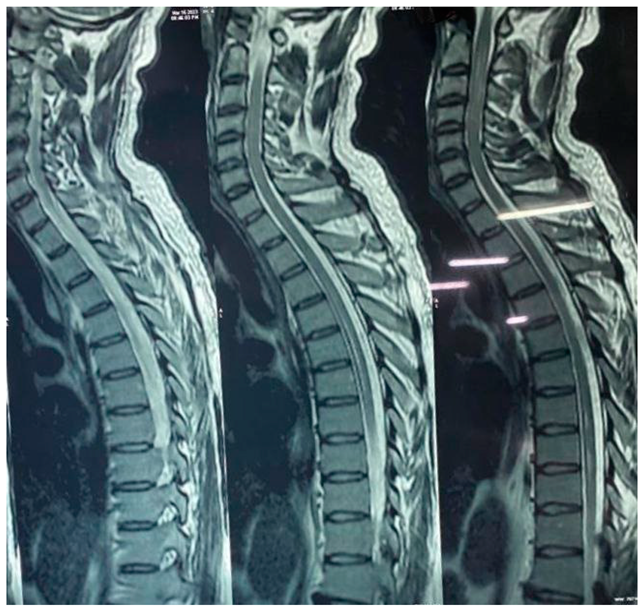

Spine:

Long segment intramedullary T2W / STIR hyperintense signal changes seen involving cervical and dorsal cord extending from C2 to upto D11 level. It is seen involving entire circumferential of cord in cervical region and central cord in dorsal region.

Preprints 95284 i002

IMPRESSION:

• Bilateral optic neuritis.

• Brain appears unremarkable.

• Abnormal signal /oedema involving spinal cord.

Imaging appearance may represent NEUROMYELITIS OPTICA (NMO).